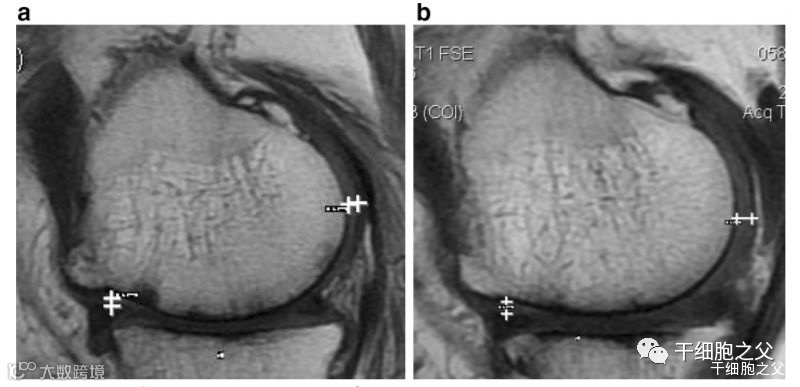

研究结果:治疗后,2年后WOMAC评分也得到改善。6分钟内步行距离也显著增加。60%的病人的软骨体积增加。

▲如上图所示,左图为治疗前,右图为治疗后,白色“+”处示意软骨增厚。